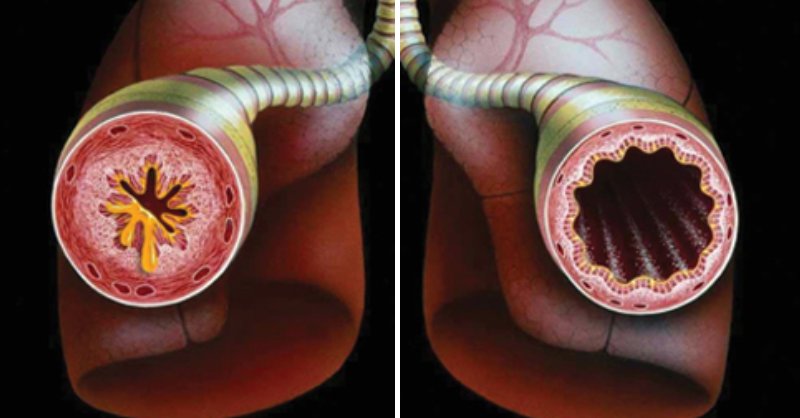

1 Cup to Cleanse Your Lungs of Phlegm and Toxins

If it feels like you can’t seem to kick a cold or your allergies are worsening, you’re in good company. Millions of people live with chronic respiratory issues...